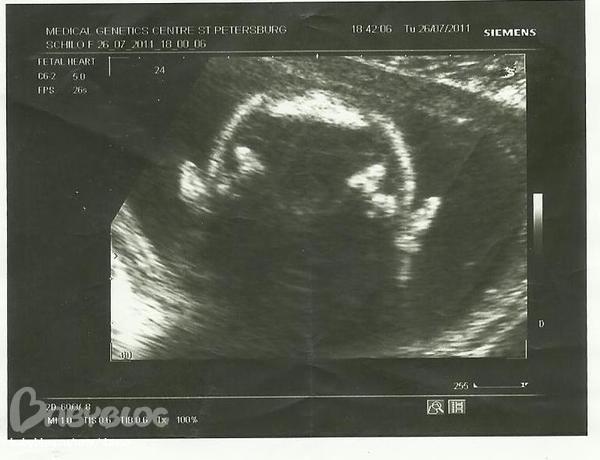

нашла с узи фото,там у Ксеньки уши видно)))

на узи ей 5 месяцев!